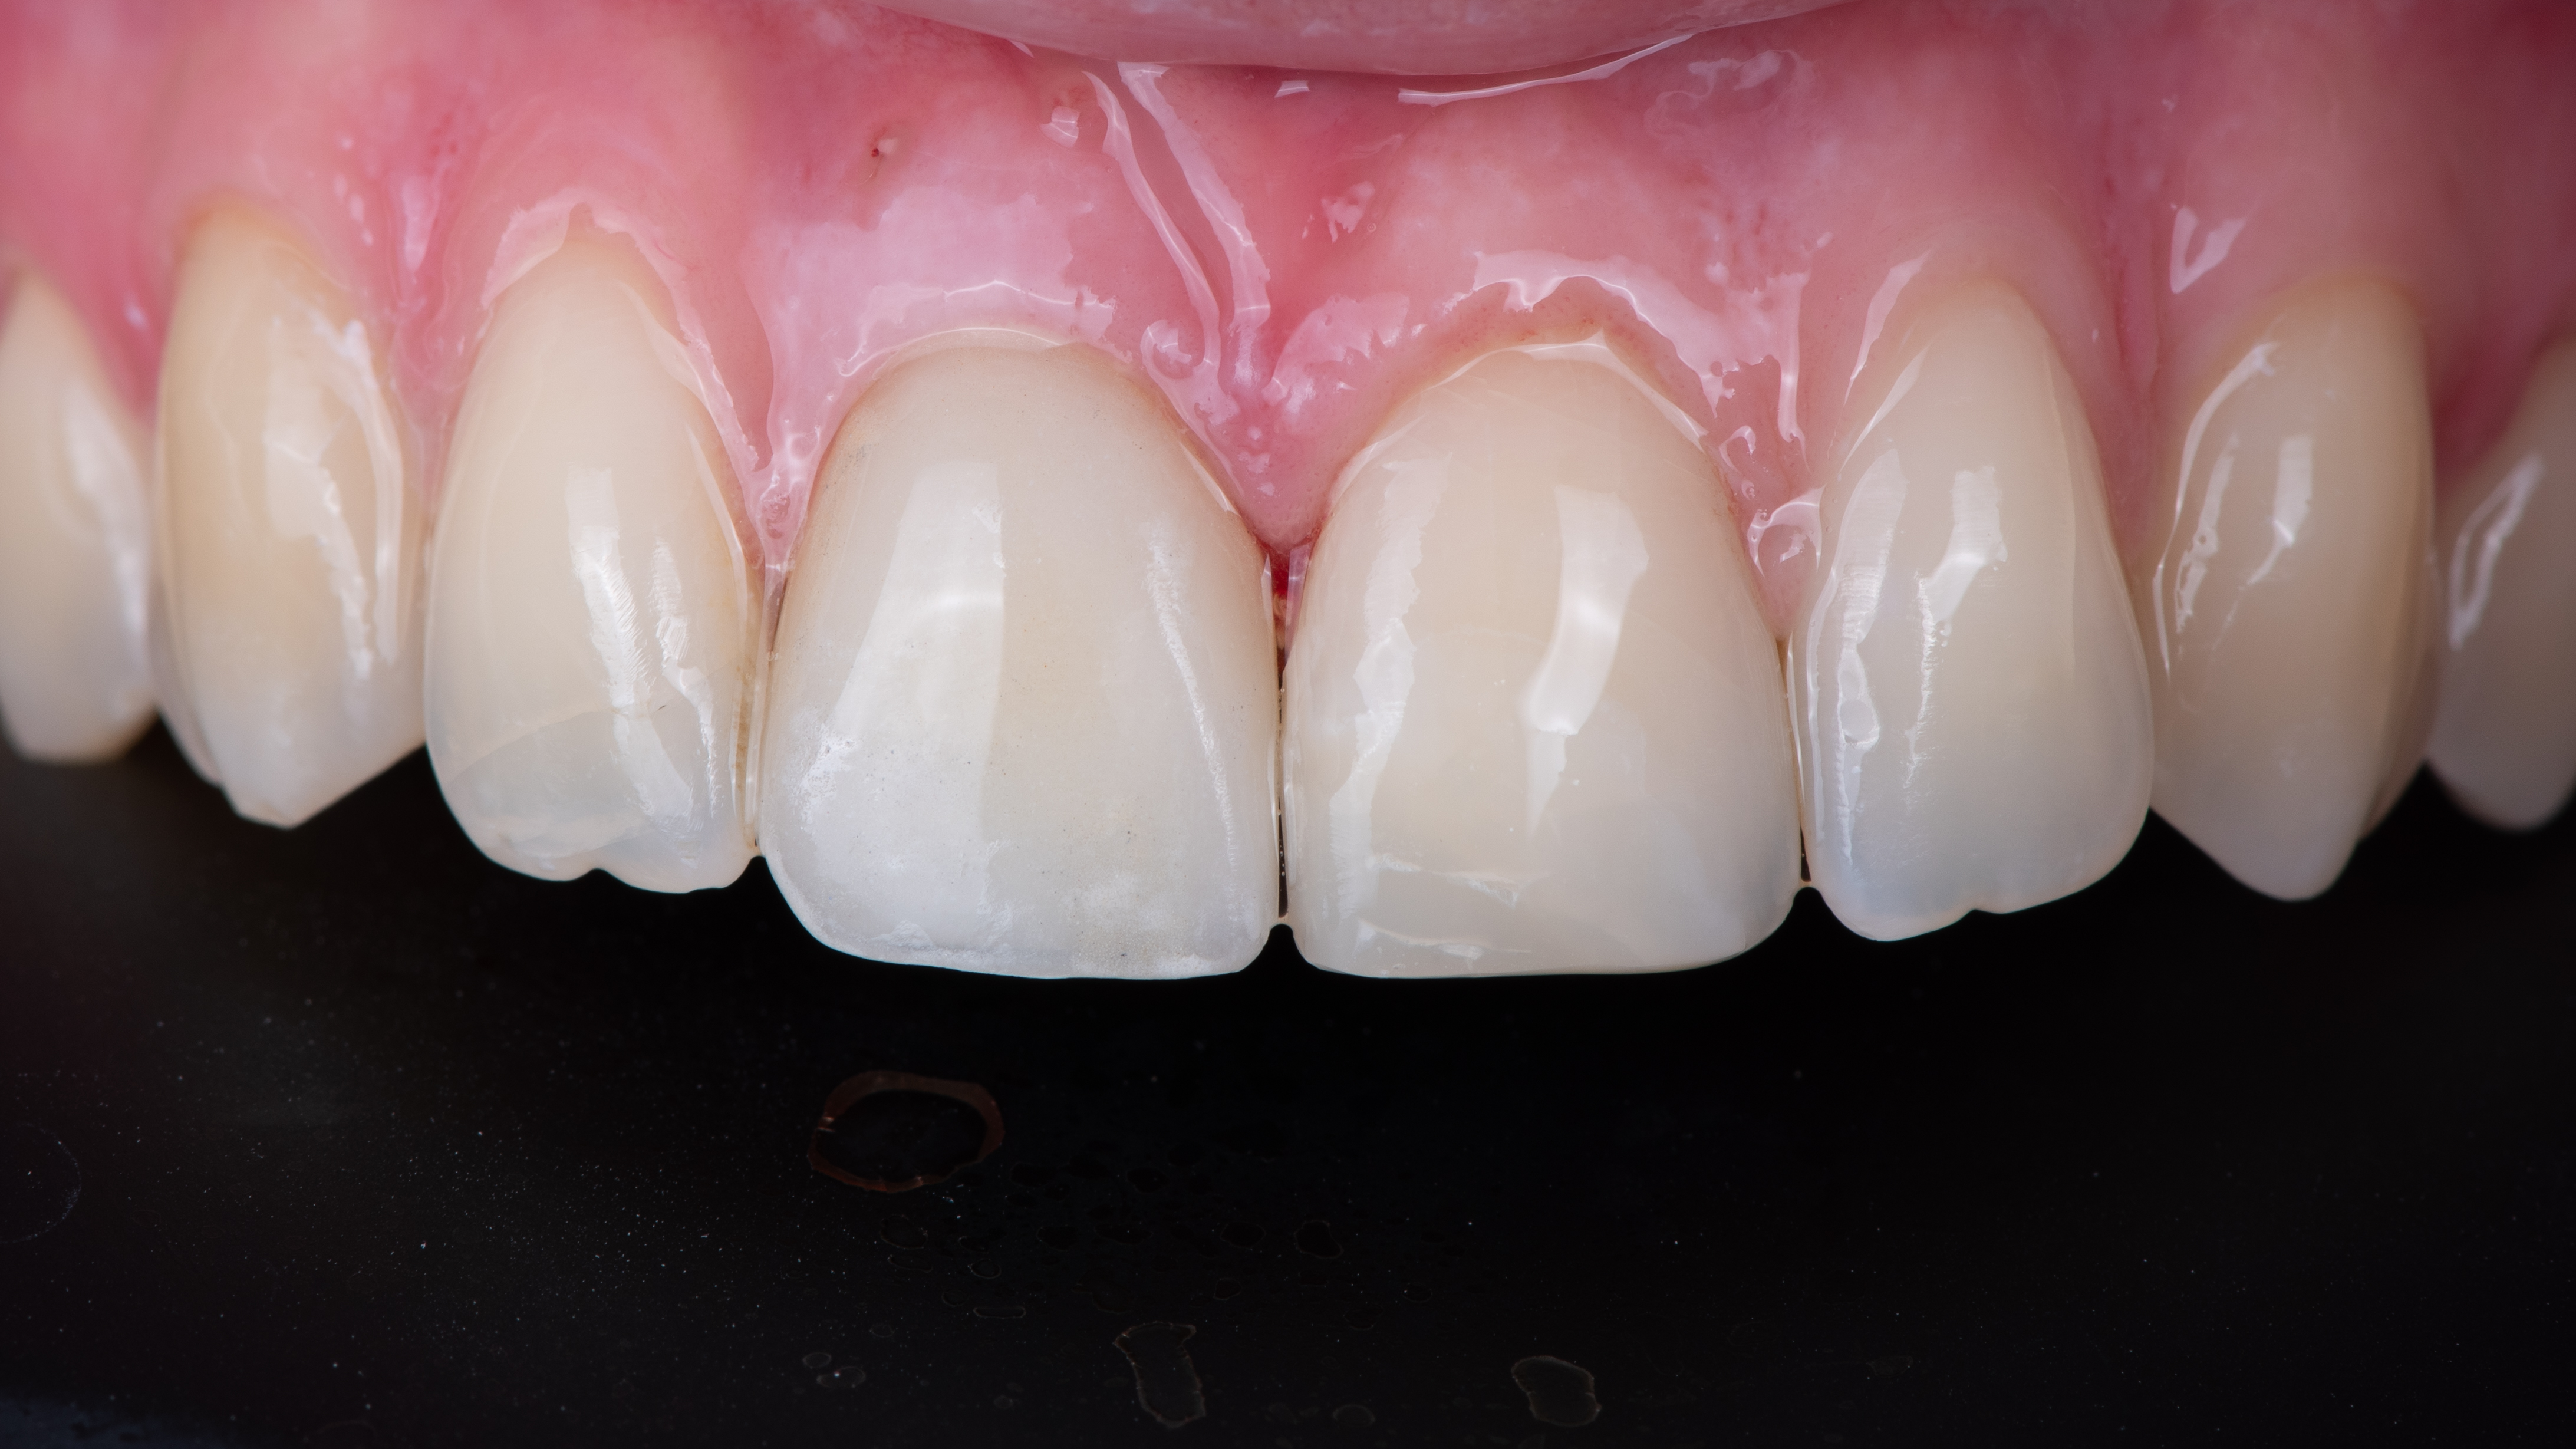

La patiente revient pour la pose de la prothèse d’usage. Nous réalisons donc un essayage de cette prothèse d’usage avant de réaliser le composite sur la dent 21.

Nous constatons que la cicatrisation est alors optimale et que la prothèse d’usage s’intègre parfaitement à son environnement (Photo 20).